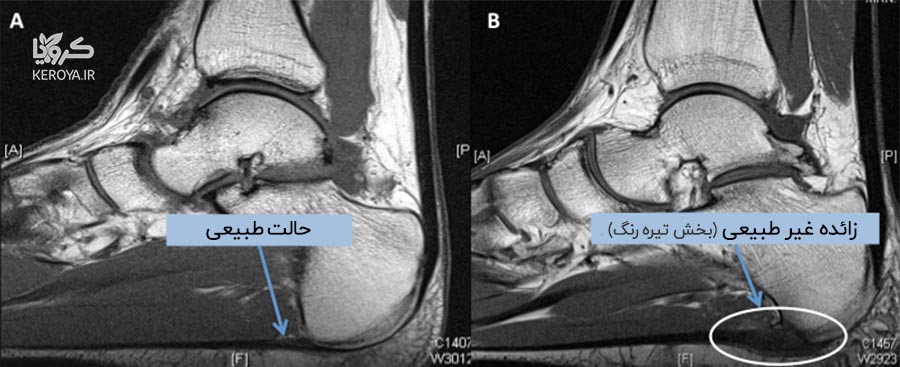

خار پاشنه یک رسوب کلسیم است که باعث بیرون زدگی استخوانی در زیر استخوان پاشنه می شود. در یک اشعه ایکس ، خار پاشنه می تواند تا نیم اینچ به جلو گسترش یابد. بدون وجود شواهد اشعه ایکس قابل تشخیص است، این بیماری گاهی اوقات به عنوان “سندرم خار پاشنه” شناخته می شود. اگرچه خار پاشنه اغلب بدون درد است، اما می تواند باعث درد پاشنه شود. آنها غالباً با فاسئیت کف پا یا التهاب دردناک باند رشته ای بافت همبند (فاسیای کف پا) همراه هستند. این ناحیه در امتداد پایین پا قرار گرفته و استخوان پاشنه را به انگشتان پا متصل می کند.

خار پاشنه هنگامی ایجاد می شود که رسوبات کلسیم در زیر استخوان پاشنه جمع می شود، این فرآیند معمولاً در طی چند ماه اتفاق می افتد. خار پاشنه اغلب به دلیل کشیدگی عضلات پا و رباط ها، کشش فاشیای کف پا و پارگی مکرر غشایی است که استخوان پاشنه را می پوشاند. خار پاشنه مخصوصاً در بین ورزشکارانی دیده می شود که فعالیت آنها شامل مقدار زیادی دویدن و پریدن است.